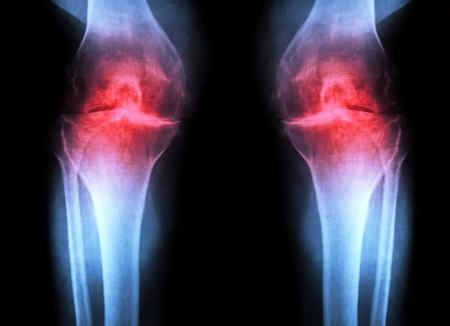

آزمایش موفقیتآمیز داروی جدیدی که میتواند «آرتروز» را درمان کند

این درمان بهجای تسکین نشانهها، عامل زمینهای آرتروز را هدف میگیرد. این بیماری حادشونده مفصلی حدود یکپنجم بزرگسالان ایالات متحده را درگیر میکند و سالانه حدود ۶۵ میلیارد دلار هزینهی مستقیم مراقبتهای سلامت ایجاد میکند. در حال حاضر هیچ دارویی وجود ندارد که بتواند روند بیماری را متوقف یا معکوس کند و مدیریت درد و تعویض مفصل گزینههای اصلی درمان هستند.

آرتروز زمانی رخ میدهد که مفصل بر اثر پیری، آسیب یا چاقی تحت فشار قرار گیرد. کندروسیتها شروع به آزادسازی مولکولهای پیشالتهابی و تجزیهی کلاژن (پروتئین ساختاری اصلی غضروف) میکنند. با از دست رفتن کلاژن، غضروف نازک و نرم میشود و التهاب همراه، تورم و درد مفصل را (که از ویژگیهای بارز بیماری است) ایجاد میکند. در شرایط عادی، غضروف مفصلی بهندرت بازسازی میشود. اگرچه برخی جمعیتهای فرضی از سلولهای بنیادی یا پیشسازِ قادر به تولید غضروف در استخوان شناسایی شدهاند، تلاشها برای یافتن جمعیتهای مشابه در غضروف مفصلی موفقیتآمیز نبوده است.